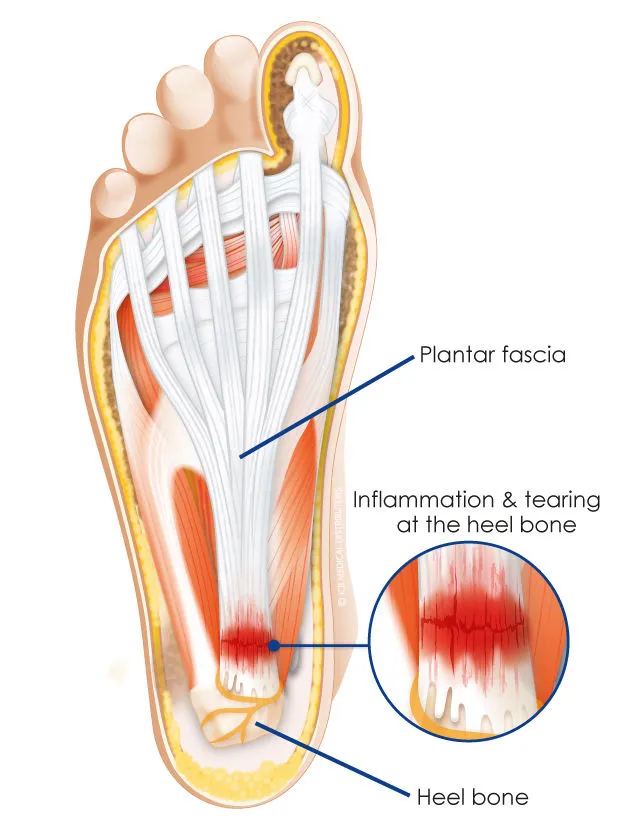

족저근막이 충격을 받는 경우는 발이 지면에 닿는 순간 발 뒤꿈치(족저근막)가 직접적으로 받는 충격과 발바닥의 이동, 발목의 각도 변화 등에 의한 발바닥 방향으로 길게 늘어져 있는 족저근막의 수축과 이완에 의한 충격 두 가지의 경우가 가장 일반적입니다.(전자는 많이 인식하고 있지만 후자의 경우에 대하여 생각하는 경우는 많지 않습니다.)

일반적으로 걸을 때 뒤꿈치가 먼저 닿이게 됩니다. 이 때 족저근막염의 주 발생지인 뒤꿈치 뼈와 연결된 족저근막 부위를 지속적으로 자극하게 되니 통증을 느끼게 되고 염증이 쉽게 나을 수가 없습니다. 뒤꿈치에 닿는 충격이 강하다면 더욱 상황은 나빠질 것입니다.

당연한 이야기를 다시 정리하자면 뒤꿈치가 먼저 닿는 걸음의 경우는 당연하게 뒤꿈치와 지면이 닿을 때 족저근막의 염증 부위에 직접적인 충격을 줍니다. 이러한 충격을 완화하기 위해 앞서 설명한 쿠셔닝이 좋은 신발, 몸무게와 무거운 짐 줄이기 등의 노력이 필요하고 오래 서 있어야 할 경우 적절한 스트레칭, 높은 곳에서 뛰거나 날카로운 물체 밟지 않기 등 직접적으로 족저근막에 충격을 가하는 행위를 피하는 것이 족부 건강에 도움이 될 것입니다.

지금까지는 족저근막염 부위와 지면의 직접적인 충격을 완화시키기 위한 방법에 대한 이야기를 해보았습니다. 그러면 직접적으로 족저근막염 부위와 지면이 닿지 않도록 앞꿈치로 걷는 경우는 어떨까요?

족저근막염 부위가 직접적으로 닿지 않으니 별다른 충격을 받을 것 같지 않습니다만 앞꿈치가 지면에 닿을 때 발 뒤꿈치에서 발가락까지 연결된 족저근막이 늘어나게 되고 늘어나는 속도와 정도에 따라 자극을 받게됩니다.